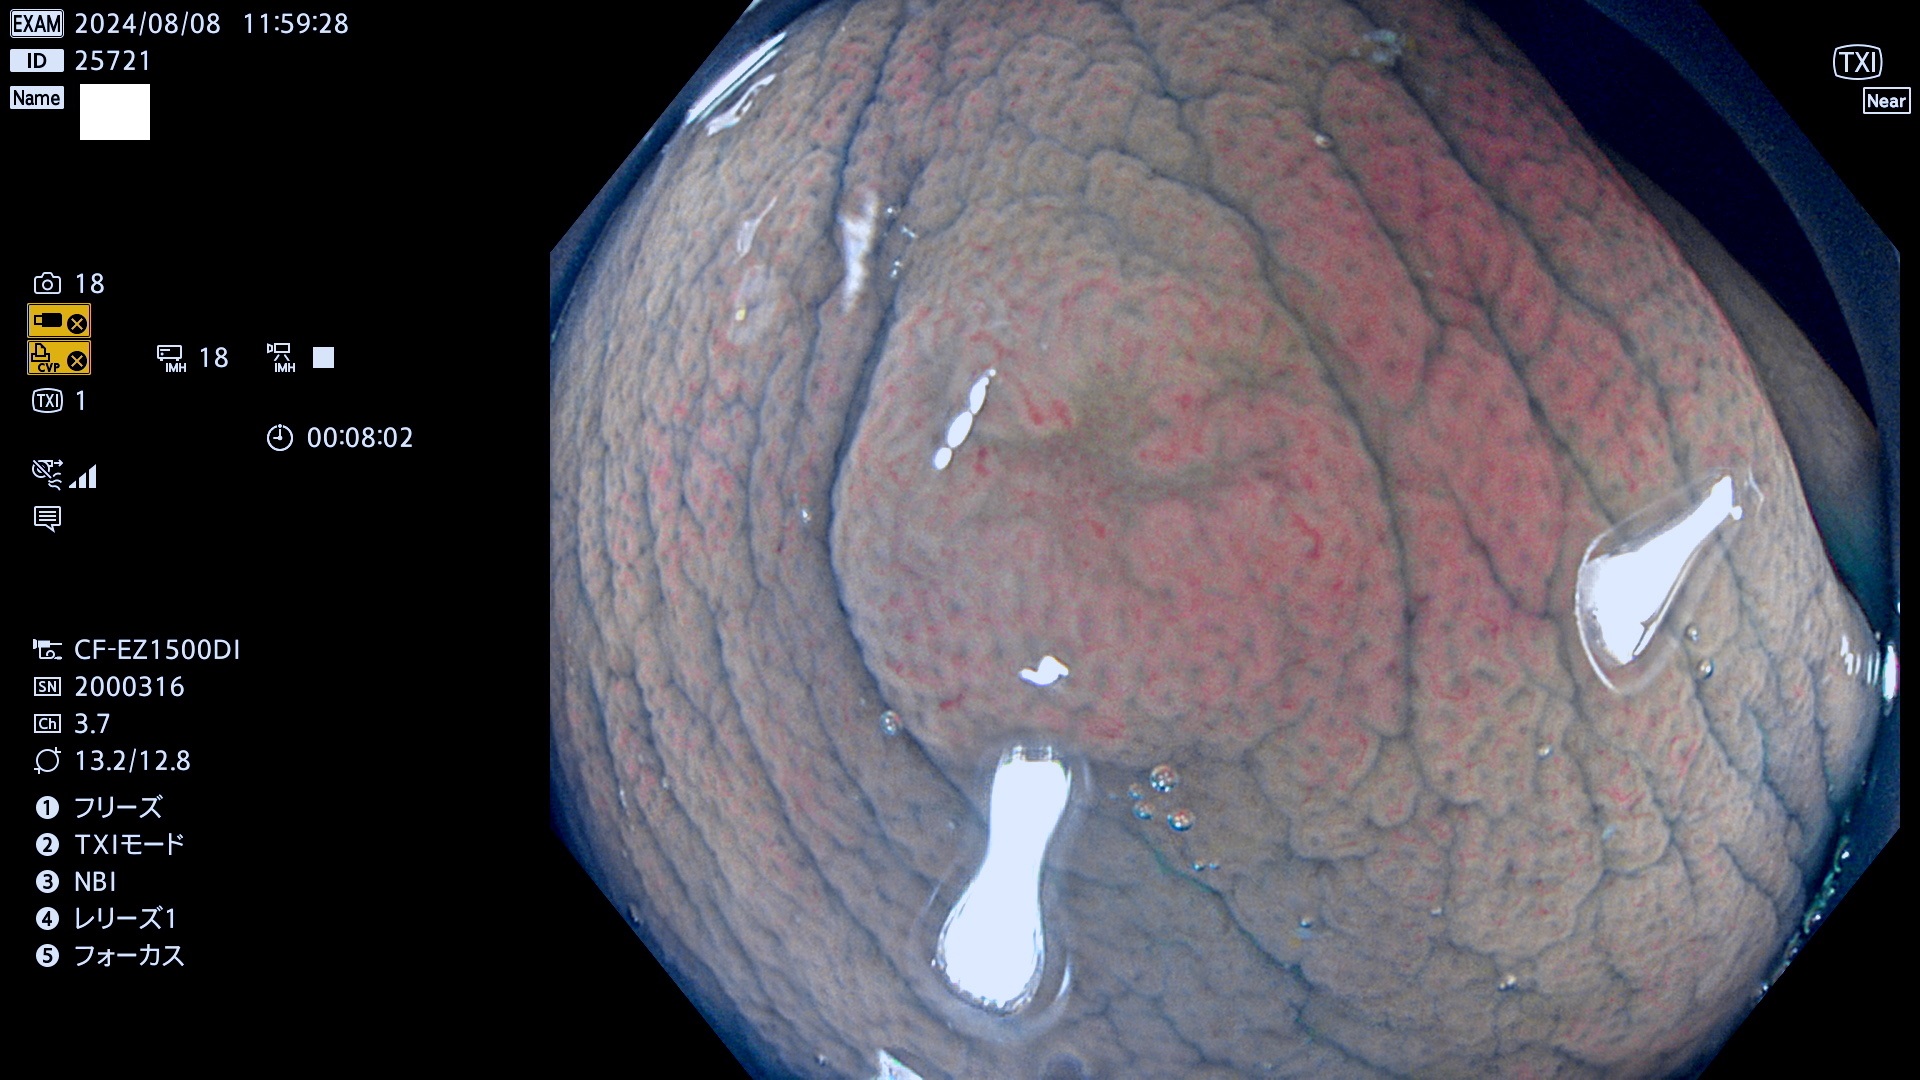

今週のUb、Uc型腺腫

完全に平坦な物をUb、陥凹している物をUcと呼びます。最も発見が難しく危険な病変です。

毎週の検査(木・金・土・日)に発見されたUb、Uc型・腺腫を、その週の日曜の夜にUPし1週間、提示します。

抽出の対象期間 2024年8月8日〜8月11の4日間(30件の検査)11件 (11/30=35%)